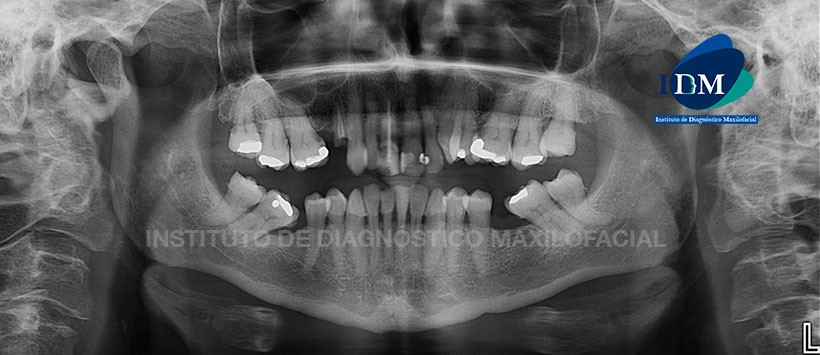

Paciente de sexo masculino de 53 años de edad acude al Instituto de Diagnóstico Maxilofacial por dolor en la pieza 21 motivo por el cual inicialmente se le realizó un estudio 2D.

A la evaluación de la radiografía panorámica (Figura 1) se pudo evidenciar la neumatización alveolar de ambos senos maxilares, placa dental mineralizada en zona cervical de todas las piezas, apiñamiento dentario del sector anterior y ausencias de algunas piezas dentarias. Sin embargo, en el sector dentario anterosuperior, lo más resaltante fue la presencia de material de obturación en la pieza 11.